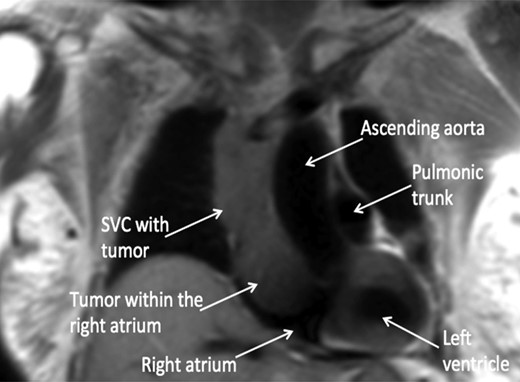

A 74-year-old female presented with facial and upper extremity swelling over the last month. The swelling was worse in the morning and improved throughout the day. The patent also reported dyspnea on exertion. A review of systems was otherwise negative. Social history was notable for 40-pack-year smoking history, but she quit smoking 12 years ago. Her vital sign were stable. Physical examination revealed mild facial swelling, non-pitting edema of the upper extremities and distention of superficial veins of the anterior chest wall and jugular veins. There were no significant laboratory abnormalities. An echocardiogram showed moderate right atrial dilation with a mobile mass in the atrial cavity prolapsing through the tricuspid valve, bowing of atrial septum from right to left consistent with increased right atrial pressure, moderate tricuspid regurgitation and normal left ventricular ejection fraction with no regional wall motion abnormalities. Cardiovascular magnetic resonance imaging revealed a 9.9 × 4.3 cm heterogeneous mass admixed with thrombus in the anterior mediastinum compressing the SVC and endovenously extending into the right atrium (Figs 1–3). Anticoagulation with heparin drip was initiated. A computed tomography (CT)-guided biopsy revealed a tan-colored mass with CD5 lymphocyte predominance, inconspicuous epithelial cells positive for P63 expression and cytokeratin AE1/AE3 that was morphologically consistent with thymoma type B1.

CMR coronal view: anterior mediastinal mass invading superior vena cava and extending into the right atrium.